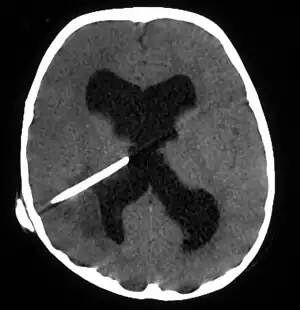

CT guided stereotactic aspiration is also indicated in the treatment of brain abscess. The use of pre-operative imaging, intervention with post-operative clinical and biochemical monitoring used to manage brain abscesses today dates back to the Pennybacker system pioneered by Somerset, Kentucky-born neurosurgeon Joseph Buford Pennybacker, director of the neurosurgery department of the Radcliffe Infirmary, Oxford from 1952 to 1971. [10]